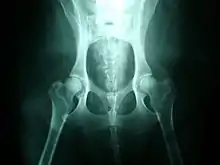

صورة بالأشعة السينية لحوض كلب طبيعي

غالبًا ما تشتمل برامج التكوين في التكنولوجيا البيطرية وعلوم الحيوان على دروس تشريح الحيوانات. تشمل برامج الطب البيطري في العادة دورات تدريبية في علم التصوير الشعاعي التشريحي (بالإنجليزية: Radiographic anatomy)، حيث يتعلم الطلاب كيفية أخذ الأشعة السينية من العظام والأنسجة الرخوة.